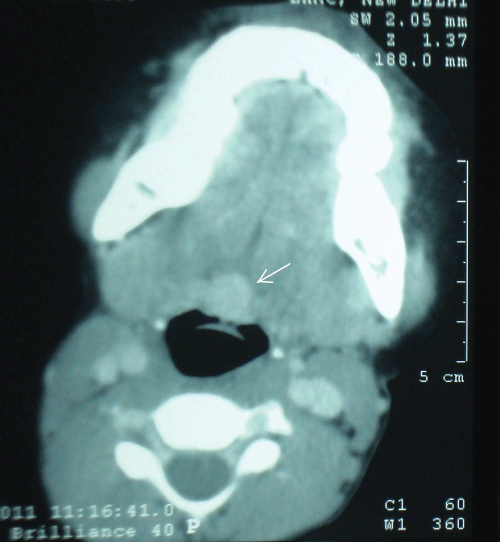

A 10 year old female child was referred to us from the paediatric department with the chief complaints of chronic cough and an occasional history of odynophagia for the past 6 months, especially following attack of upper respiratory tract infection. Important causes of chronic cough like infection [including TB], allergy, asthma and drug intake [e.g. ACE inhibitors] were ruled out and patient was being treated on the lines of reflux laryngopharyngitis with no improvement. An ENT opinion was sought for chronic sinusitis and tonsillitis. ENT evaluation revealed a small midline mass covered with normal mucosa at the base of tongue. CT scan done to delineate the said lesion showed a well defined intensely enhancing mass lesion in the base of tongue in the midline [Figure 1 and Figure 2]. On the basis of CT scan a differential diagnosis of midline branchial cyst, thyroglossal cyst, epidermoid and sebaceous cyst, lingual thyroid, lymphangioma and tumours [adenoma, fibroma & salivary gland tumour] were considered. However, evaluation of the CT scan showed the absence of normal thyroid tissue in the neck. A diagnosis of lingual thyroid was made and confirmed by Tc-99m pertechnetate radionuclide scan which showed uptake only at the base of tongue, a feature consistent with lingual thyroid [1]. Thyroid function tests were normal in the said case.

Figure 1: A hypotense, homogenous intensely enhancing lesion is noted at the base of tongue in axial.